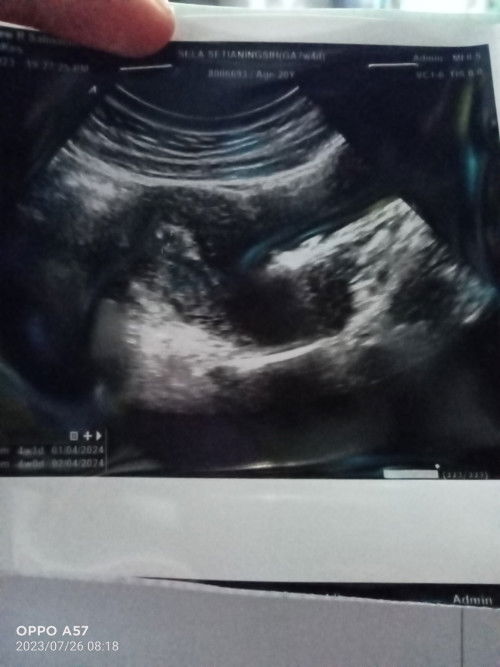

Bunda anakku umur 9bulan diare tanpa dehidrasi sudah lebih dari 10hari. Dia tetap ceria dan lagi tumgi juga. Bingung mau ngasih makan apaa, klo ngasih fortif kayak sembelit gitu. Kalo ngasih bubur nasi buatan mamahnya , malah gak dimakan. Jadi harus gimana ya? Dan gimana ya agar diare nya cepet berhenti?? Btw. Udah ke puskesmas juga cuma dikasih zinc dan oralit. #Sharing_dong_Bund #SeriusTanya #bantujawab